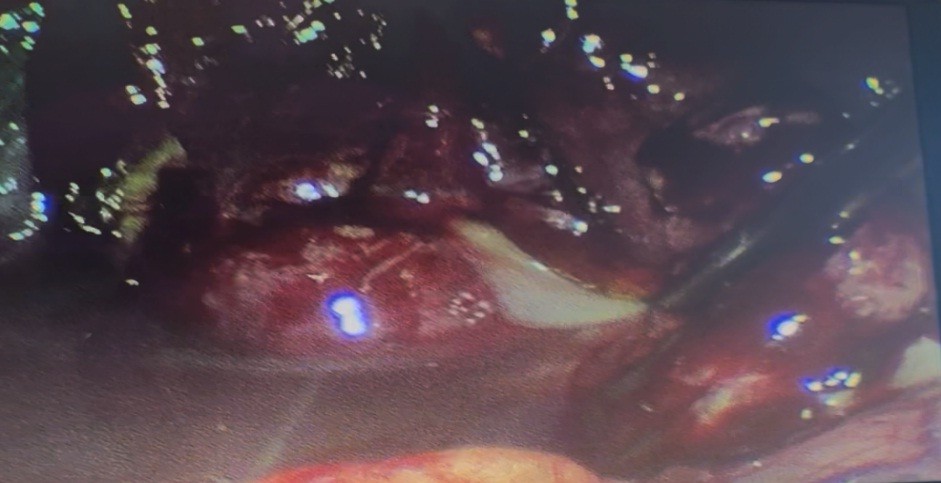

Most patients with perforated gastroduodenal ulcers underwent suturing due to late admission (Fig. 1).

Figure 1. Laparoscopic abdominal cavity sanitation